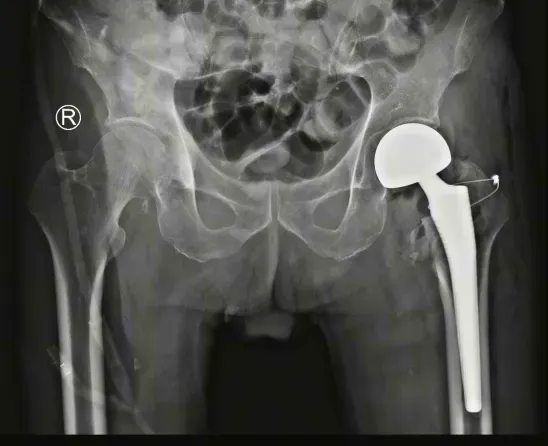

9月3日入院后第3天,任姜栋主任与团队一起,历时40分钟,为陈大爷完成了“左人工股骨头置换术+股骨转子间骨折切开复位内固定术”手术治疗。术中出血约50毫升,手术顺利完成。

▲术后复查

老年髋部骨折患者,手术方案应该如何选择?是选择内固定治疗还是关节置换方案?任姜栋主任对该病例进行了回顾。

对于股骨粗隆间骨折,内固定是常规首选方案,稳定的固定是允许患者术后早期康复和负重的基础,但内固定物螺钉的把持力与骨质疏松程度相关,老年髋部骨折患者多合并不同程度的骨质疏松,骨质的承载支撑力下降,更易发生内固定失效、螺钉退出等并发症。

髋关节置换手术也作为治疗老年股骨粗隆骨折的一种选择,其优点是可以实现早期下地活动,避免长期卧床带来的一系列并发症。因此,对于骨折粉碎严重、内固定治疗可能失败或发生骨不连的老年股骨粗隆骨折,建议首选髋关节置换手术。